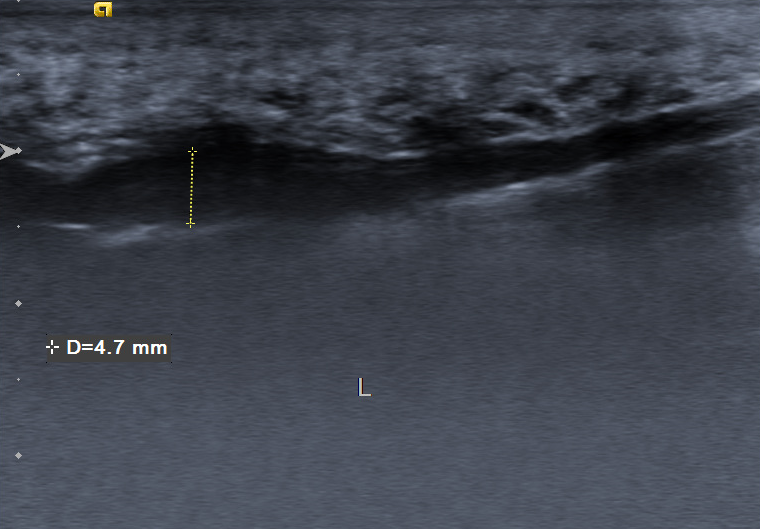

超声检查是目前诊断足底筋膜炎的一项非常实用且经济的工具。通过超声波,医生可以实时观察足底筋膜的状态,评估其是否增厚、是否有炎症,或者是否存在微小的撕裂等病变。超声还可以用来检测足底筋膜的血流情况,进一步了解炎症的程度。超声检查操作性强,且成本相对较低,因此在临床上被广泛应用于足底筋膜炎的诊断。